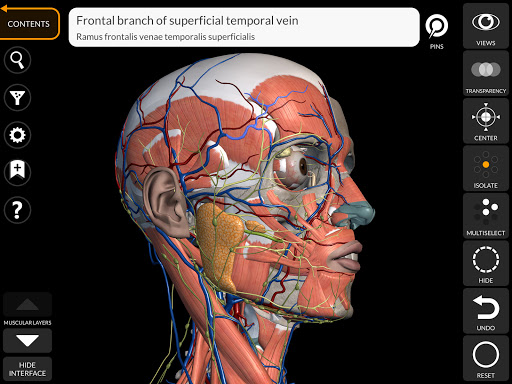

"Anatomy 3D Atlas" дозволяє легко та інтерактивно вивчати анатомію людини.

Завдяки простому та інтуїтивно зрозумілому інтерфейсу можна спостерігати кожну анатомічну структуру під будь-яким кутом.

Анатомічні 3D-моделі особливо деталізовані та мають текстури з роздільною здатністю до 4k.

• Візуалізація м’язів через рівні шарів від поверхневих донизу до найглибших

• Вибравши модель або шпильку, з’явиться відповідний анатомічний термін

• Опис м’язів: походження, приєднання, іннервація та дія

• Анатомічні терміни можуть відображатися двома мовами одночасно.